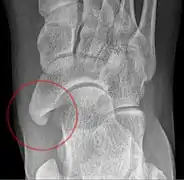

Radiological images

Lateral projection of type 2